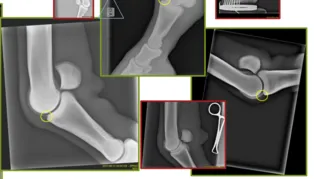

Image analysis of joints

Artificial intelligence in veterinary diagnostic imaging to classify fragments in joints. Measuring the added benefit of augmented decision-making and quality control.